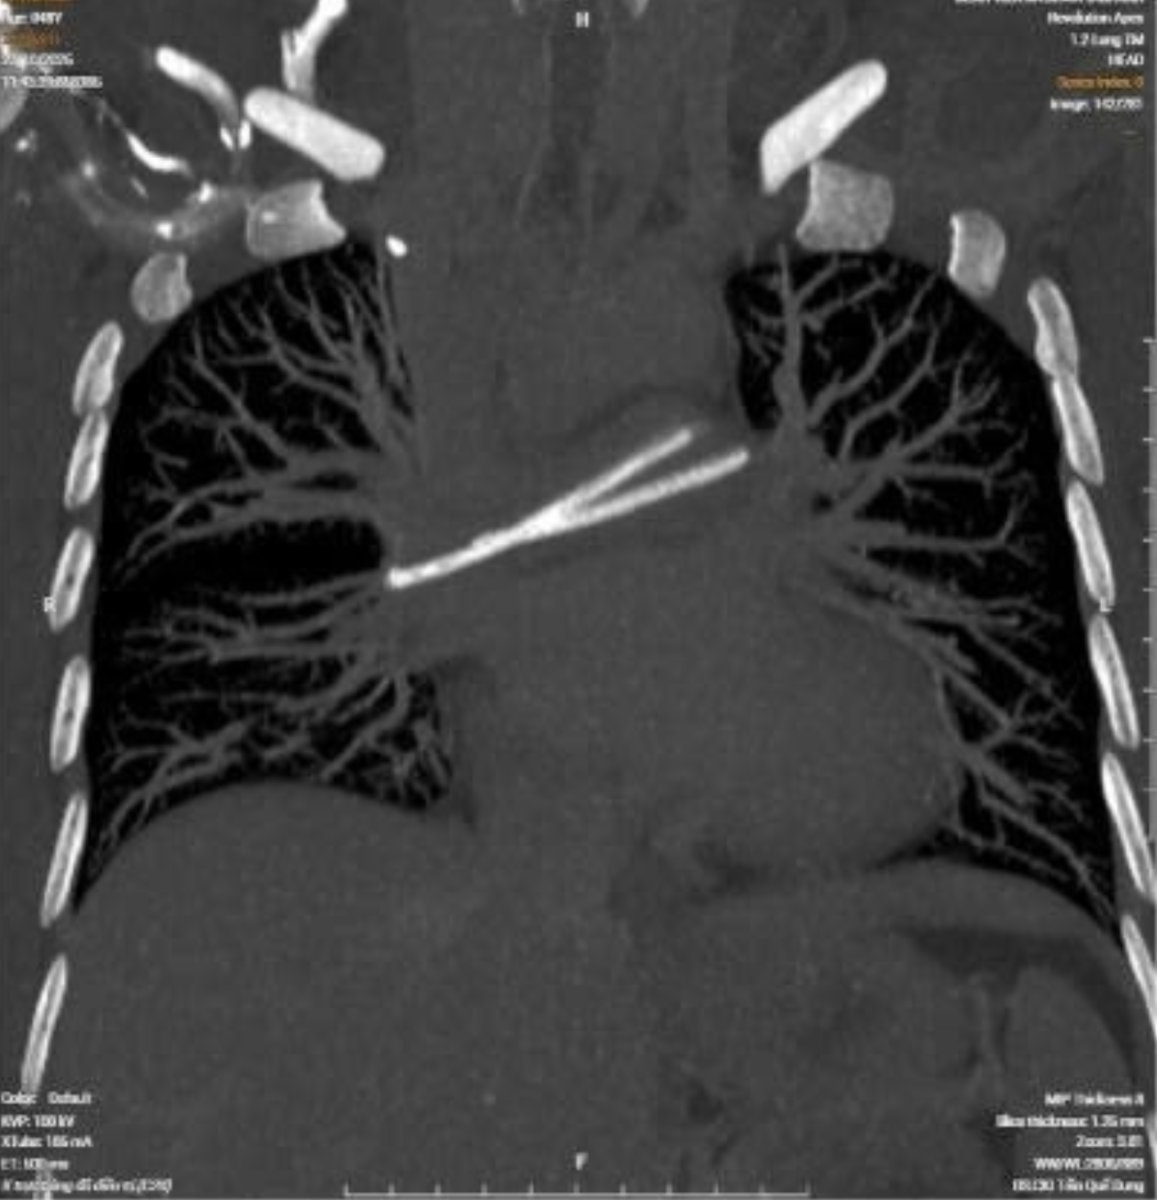

Bước ngoặt xảy ra khi bệnh nhân đi khám tầm soát tại một cơ sở y tế tư nhân. Kết quả CT ngực có tiêm thuốc cản quang khiến bác sĩ bất ngờ: một dị vật dạng ống nằm trong tim, vắt ngang vùng động mạch phổi hai bên.

Hình ảnh chụp X-quang dị vật ống truyền hóa chất bị đứt, trôi vào tim.

Khi được chuyển đến bệnh viện tuyến trên để kiểm tra lại, phim X-quang ngực cho thấy ống truyền hóa chất đã bị đứt làm hai đoạn. Một đoạn còn nằm dưới da, đoạn còn lại đã trôi theo dòng máu vào tim và mắc kẹt tại động mạch phổi – vị trí cực kỳ hiếm gặp trên lâm sàng.